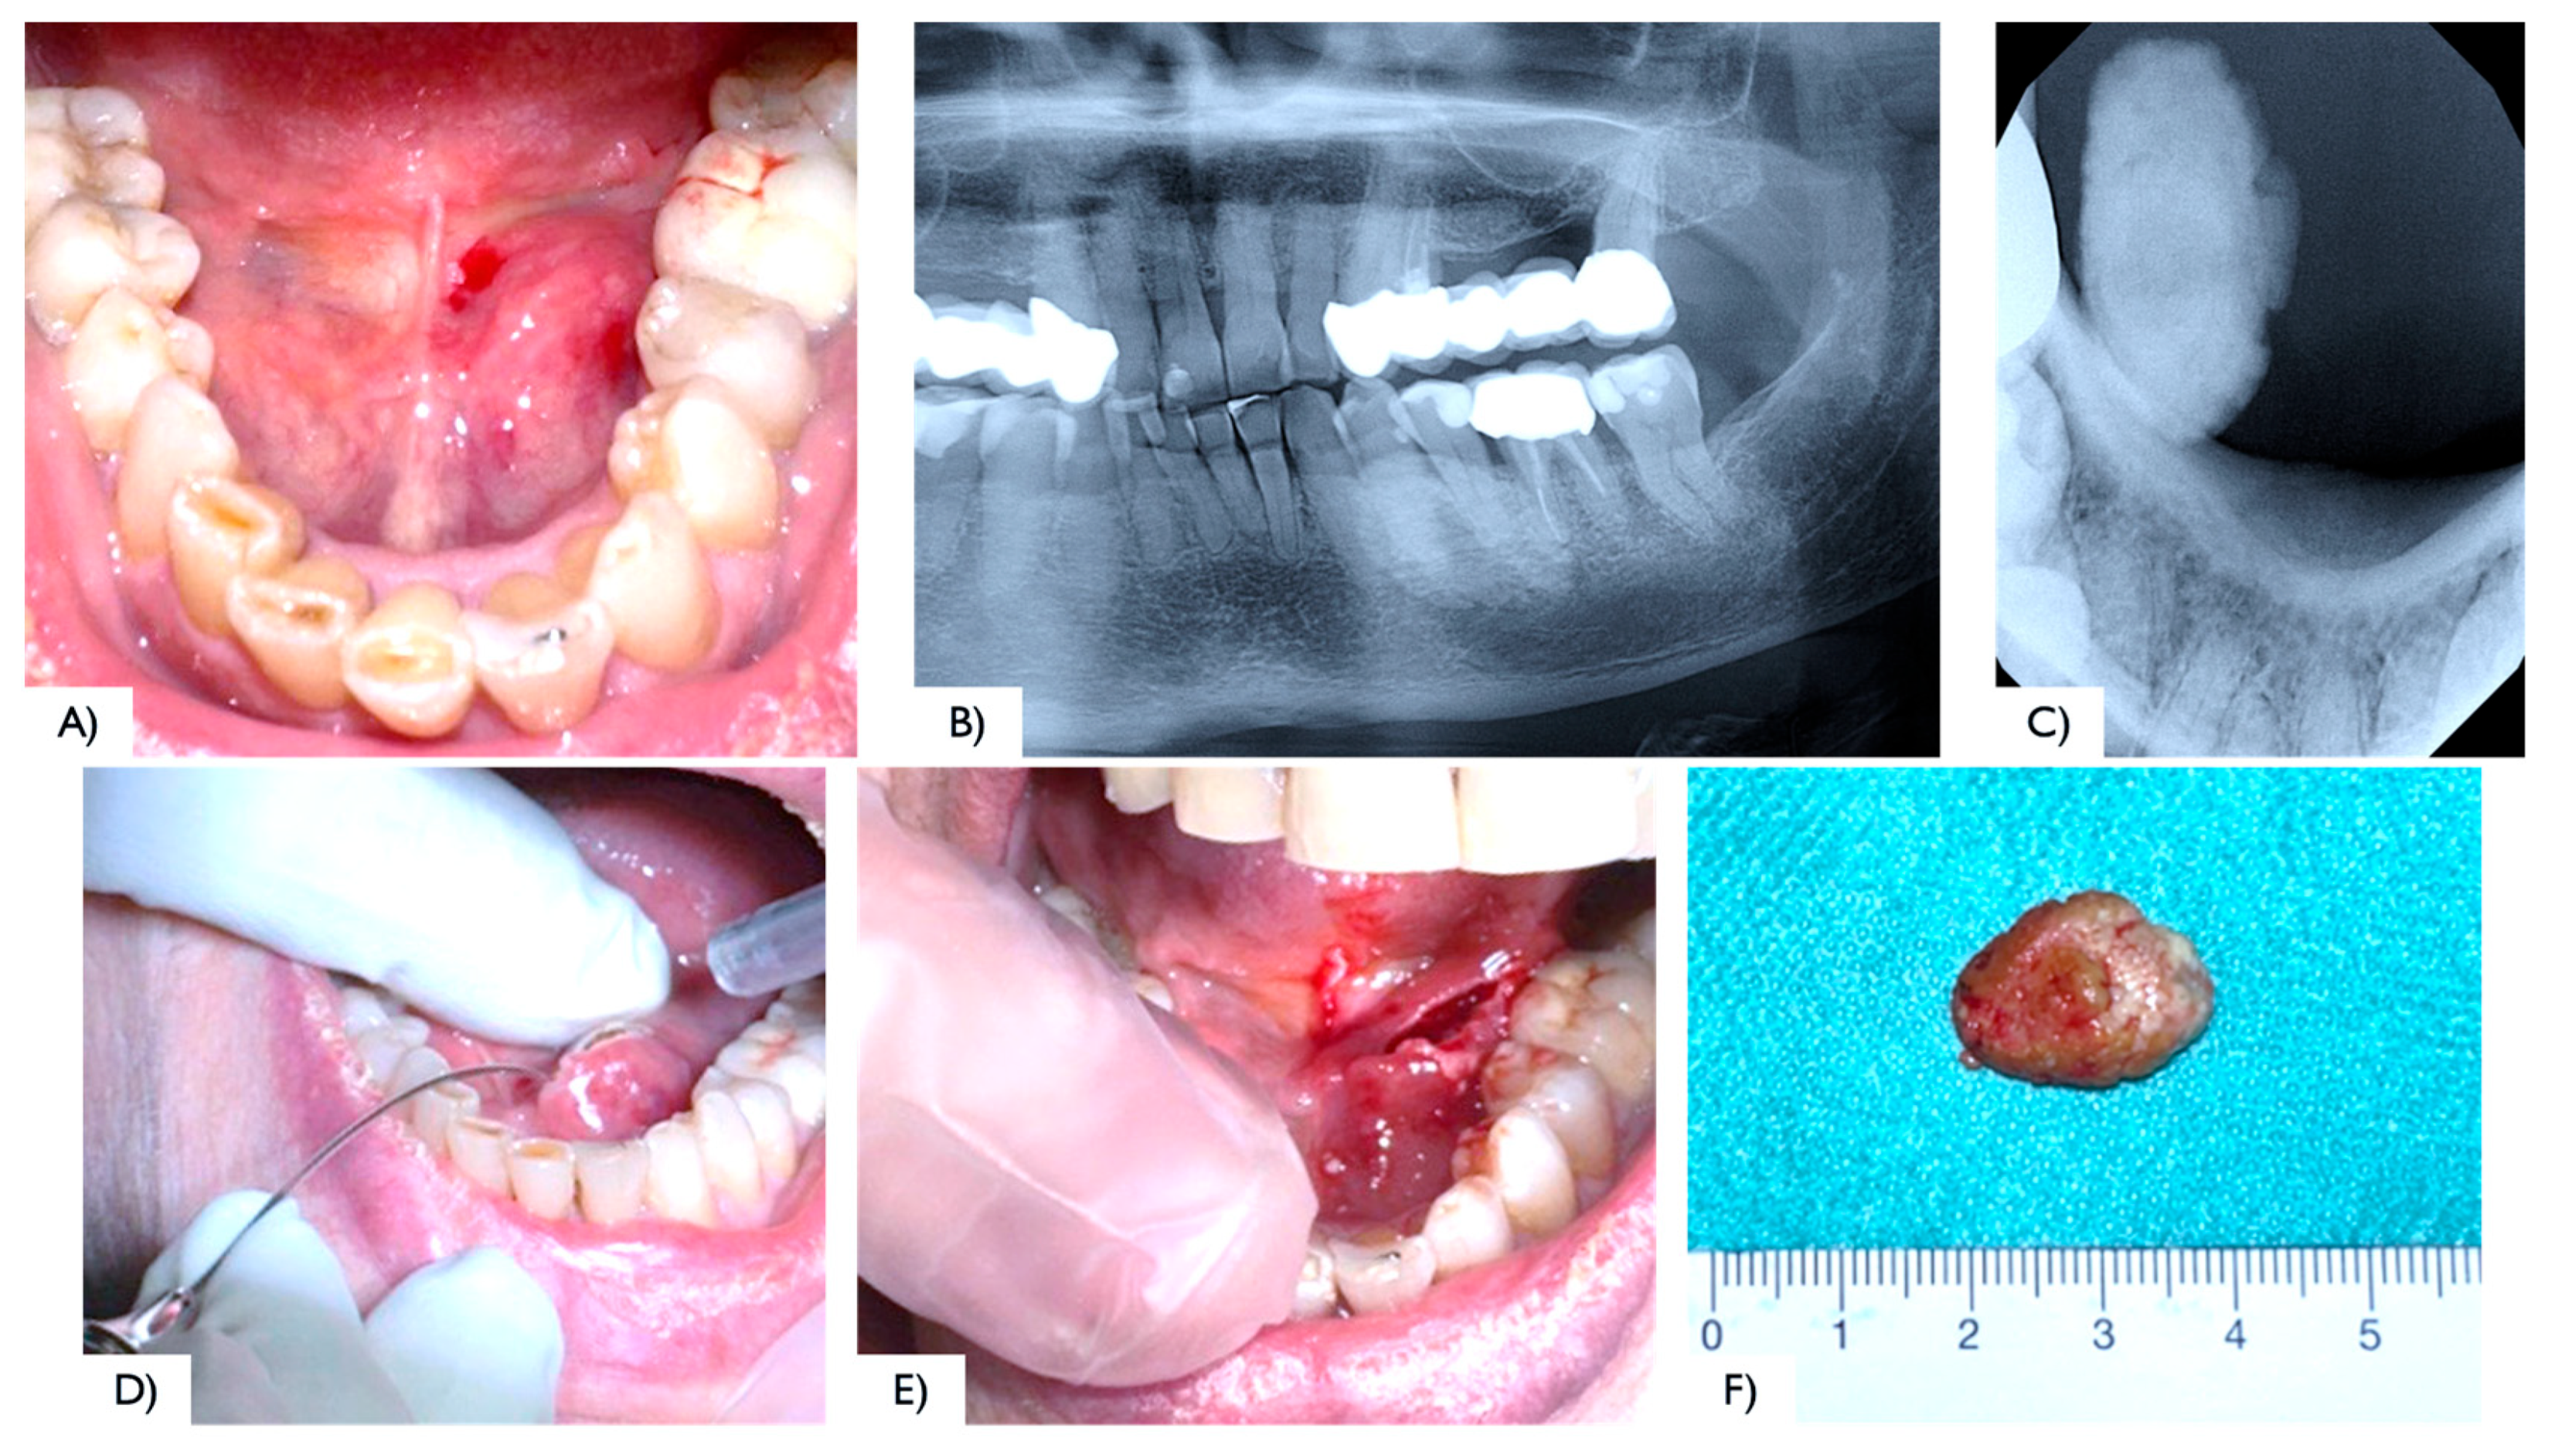

2.1. Case Report 1

2.2. Case Report 2